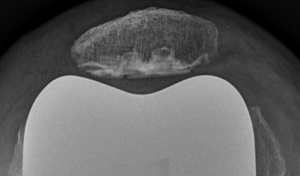

Lorsque l’usure du cartilage n’atteint qu’un compartiment sur les 3, une prothèse unicompartimentale peut-être proposée. Le plus souvent, il s’agit d’une prothèse unicompartimentale interne, plus rarement externe (environ 10 % des cas) et exceptionnellement fémoropatellaire (sur la rotule et la partie du fémur lui faisant face).

La prothèse unicompartimentale est un « resurfaçage », elle ne va pas modifier la géométrie du genou, mais va simplement se positionner à la place du cartilage retiré. Elle est composée de 3 pièces : un implant fémoral (sorte de patin), un implant tibial (embase) et un insert en polyéthylène (plastique hautement résistant) qui se loge entre les 2 composants métalliques.  L’avantage de la prothèse unicompartimentale par rapport à la prothèse totale est qu’il s’agit d’une chirurgie moins invasive, qui respecte l’enveloppe ligamentaire du genou et qui restitue une mécanique du genou que l’on peut qualifier de normale.

Certaines conditions sont indispensables pour pouvoir proposer cette intervention : faible déformation du genou, absence de raideur importante, présence du ligament croisé antérieur, absence d’obésité, absence de maladie inflammatoire du genou… Si ces critères ne sont pas réunis, il faudra s’orienter vers la prothèse totale du genou. On estime qu’environ 10 % des prothèses de genou sont unicompartimentales. Une des indications préférentielles est l’ostéonécrose du condyle fémoral (interne le plus souvent).

L’incision cutanée mesure environ 10 cm. Le premier temps opératoire consiste à explorer le genou et confirmer l’indication de prothèse unicompartimentale. Puis, à l’aide d’instruments très précis (guides de coupes), le chirurgien va retirer la zone de cartilage malade et y implanter la prothèse.